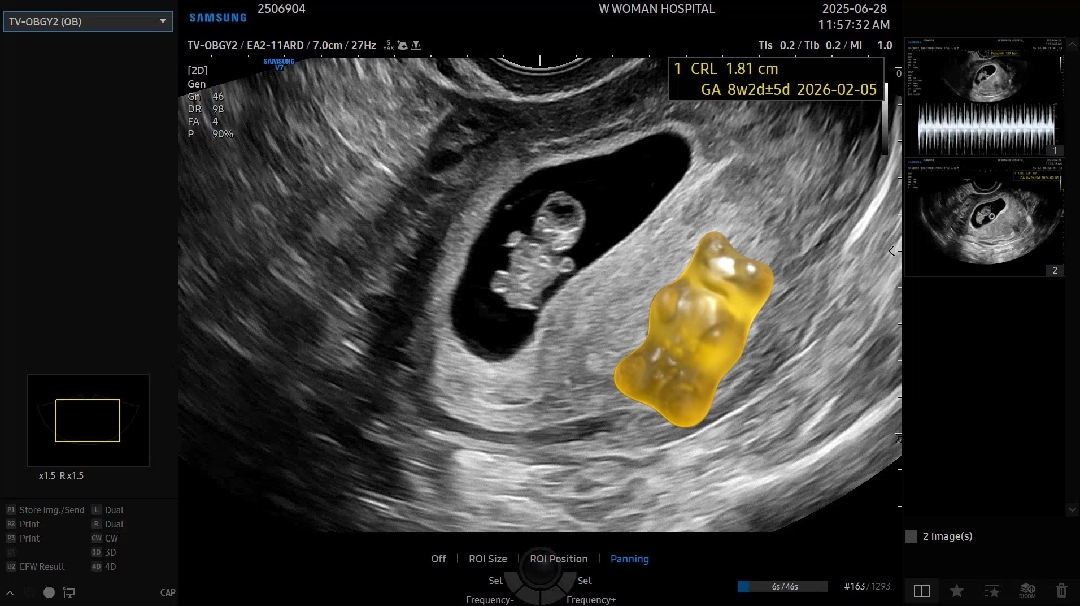

2월 5일 출산예정인 복댕이맘입니다! 8주 2일차에 젤리곰 보고 왔어요😆 아직 초기지만 진료 갈때마다 점점 자라는게 보이니까 마음이 이상?몽글?하네요ㅎㅎ